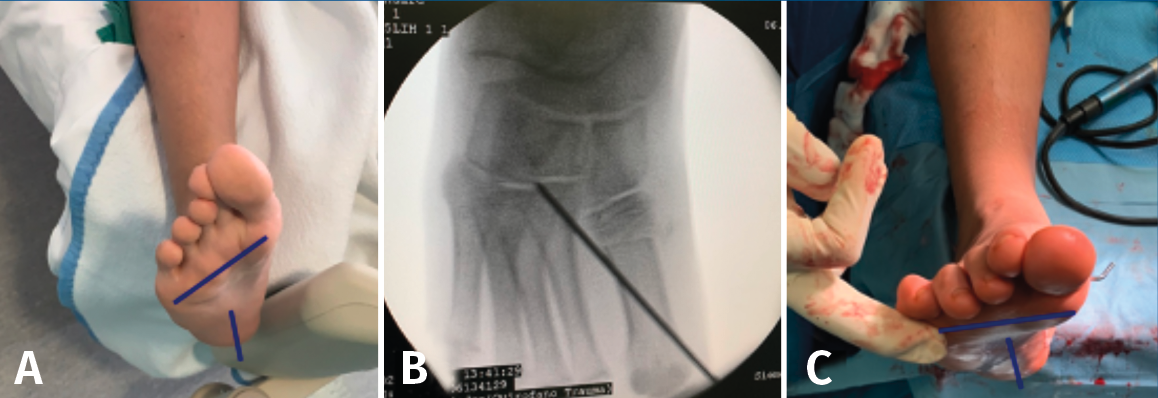

Osteotomía percutánea de verticalización de la primera cuña o del primer metatarsiano

La técnica quirúrgica (Figura 14) es la siguiente: se realiza una osteotomía percutánea de sustracción plantar en el tercio proximal del primer metatarsiano con osteoclasia dorsal, consiguiendo una verticalización de este, que conducirá a una pronación del antepié.

Figura 14. Osteotomía percutánea de verticalización del primer metatarsiano. A: imagen clínica donde se aprecia supinación del antepié; B: osteotomía percutánea de sustracción plantar en el tercio proximal del primer metatarsiano, más osteosíntesis con aguja de Kirschner; C: imagen clínica, tras la osteotomía, donde se aprecia la corrección de la supinación del antepié.

De la misma manera, se puede realizar esta osteotomía a nivel de la primera cuña con cierre plantar. La osteosíntesis en el niño se puede realizar con una AK entre el primer metatarsiano y tarso que se retira en consulta.